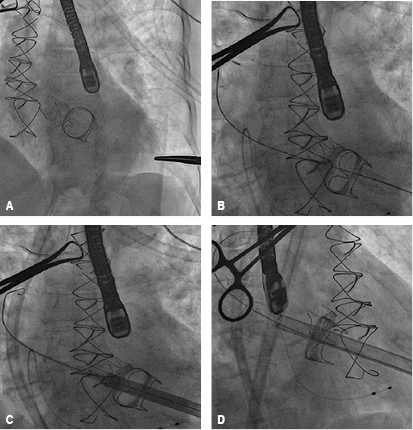

Held on January 22, 2016, prior informed consent of the patient and family. Under general anesthesia with endotracheal intubation, it proceeds to perform asepsis and antisepsis of both femoral regions, with modified Seldinger technique are punctured left femoral artery and right femoral vein, placing introducers of 5 and 6 French (fr), temporary pacemaker is placed in the right ventricle without complications and adequate capture is confirmed, remaining on guard. Then, a left anterolateral thoracotomy is performed at the fifth intercostal space, the pericardium is incised longitudinally and marsupialized, tucks are placed in snuff bag form with prolene 2-0 to expose the left ventricular apex without penetrating ventricular cavity, near the apex and lateral to the anterior descending artery with modified Seldinger technique the apex is punctured at the level of the left ventricle and the femoral introducer 6 fr is advanced, the mitral bio-prosthetic valve is intersected with a 0.035 mm teflonated guidewire with interchange curve, the multipurpose catheter 1.5 fr is advanced through which a guide "Amplatz extra-stiff" is swapped to the left pulmonary vein (Figure 6), introducer Ascendra of 24 fr is placed and through this the delivery transapical system with an Edwards Sapien #26 (Edwards Lifesciences, Irvine, California) valve, after corroborating the proper position with fluoroscopy in right anterior oblique projection, the valve is released successfully (Figure 7). Transesophageal echocardiography performed during the procedure shows the dysfunctional prosthetic mitral valve with a mean gradient of 25 mmHg, the apex is located for the surgical intervention, and is verified in two and four cameras projection, coaxiality with needle and introducer is verified, biological prosthetic valve is intersected with guide and introducer, the deployment of percutaneous mitral valve on longitudinal axis of 3 cameras (120o) is monitored, and the proper position of the valve is verified, without identifying paravalvular leak, appropriate opening/closure and mean gradient of 3 mmHg (Figure 8). Introductors and delivery system are removed, the apex is closed by knotting the two sutures in bag snuff previously set, a pericardial effusion was shown by transgastrical projection, restricted exclusively to posterior wall without hemodynamic effects on right cavities, monitoring is performed by subcostal window observing a separation of sheets of 15mm, repair apex was performed with prolene 2-0 due to a left ventricle tear, contained without further complication; pericardium and chest wall is closed in layers, prior echocardiography subcostal drain is placed, and pacemaker is maintained with stimulation. Fluoroscopy time of 24 minutes, use of 22 milliliters of contrast, removing introducers and considering the procedure as successful.

Figure 6: Step by step of transcatheter mitral valve-in-valve implantation via a transapical approach: mitral bio-prosthetic valve in situ, seen by fluoroscopy (A). Mitral bio-prosthetic valve intersected by "Amplatz extra-stiff" guidewire and advanced to the left pulmonary vein (B). Ascendra introducer is placed and through this the delivery system (C and D).

Figure 7: Step by step of transcatheter mitral valve-in-valve implantation via a transapical approach: an Edwards Sapien #26 valve (Edwards Lifesciences, Irvine, California) is positioned within the Carpentier-Edwards biological valve #27 (A), successfully deployed (B), removing delivery system (C) and corroborating the proper position with fluoroscopy in right anterior oblique projection (D).